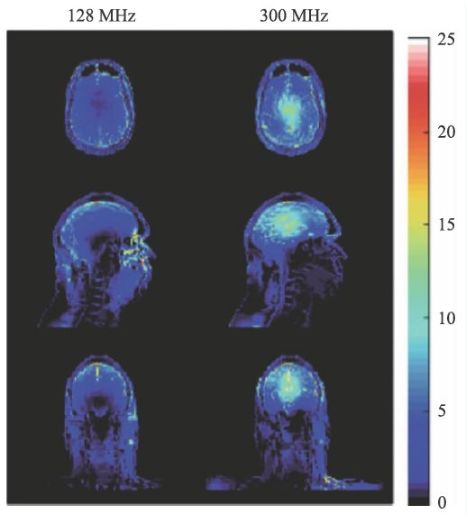

SAR值升高是射频场另一个问题,随着射频频率的提高,组织对射频能量的吸收急剧上升,可导致组织局部的温度升高。SAR值的计算可由式9表示。

σ为组织电导率,ρ为组织密度。对于SAR值各国和国际组织均有严格的限制,因为过量的射频能量的吸收可能会对受试者造成危害。

图14 是一个SAR值对大脑温度升高的一个仿真结果[14],对于平均SAR=3 W/kg的头部扫描,7 T(右侧)下的温度升高显著高于3 T(左侧)。因此在超高MRI中均需要配置一个可靠的SAR值监控装置。

图14 局部SAR值的仿真结果